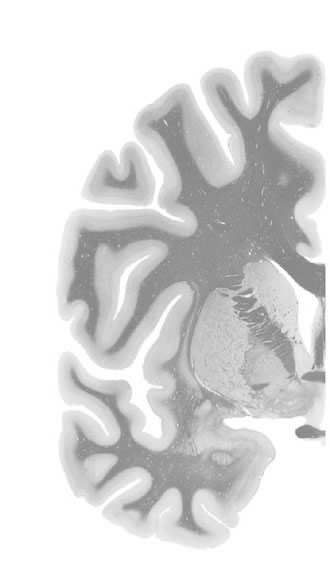

Hi-Resolution Sections · Cells (Nissl Staining) · Virtual Microscopy

Frontal sections (Nissl) from the Atlas Brain:

Slice ID:

r3-1278

Plate NR:

ca 24-25

Position:

3,3 mm